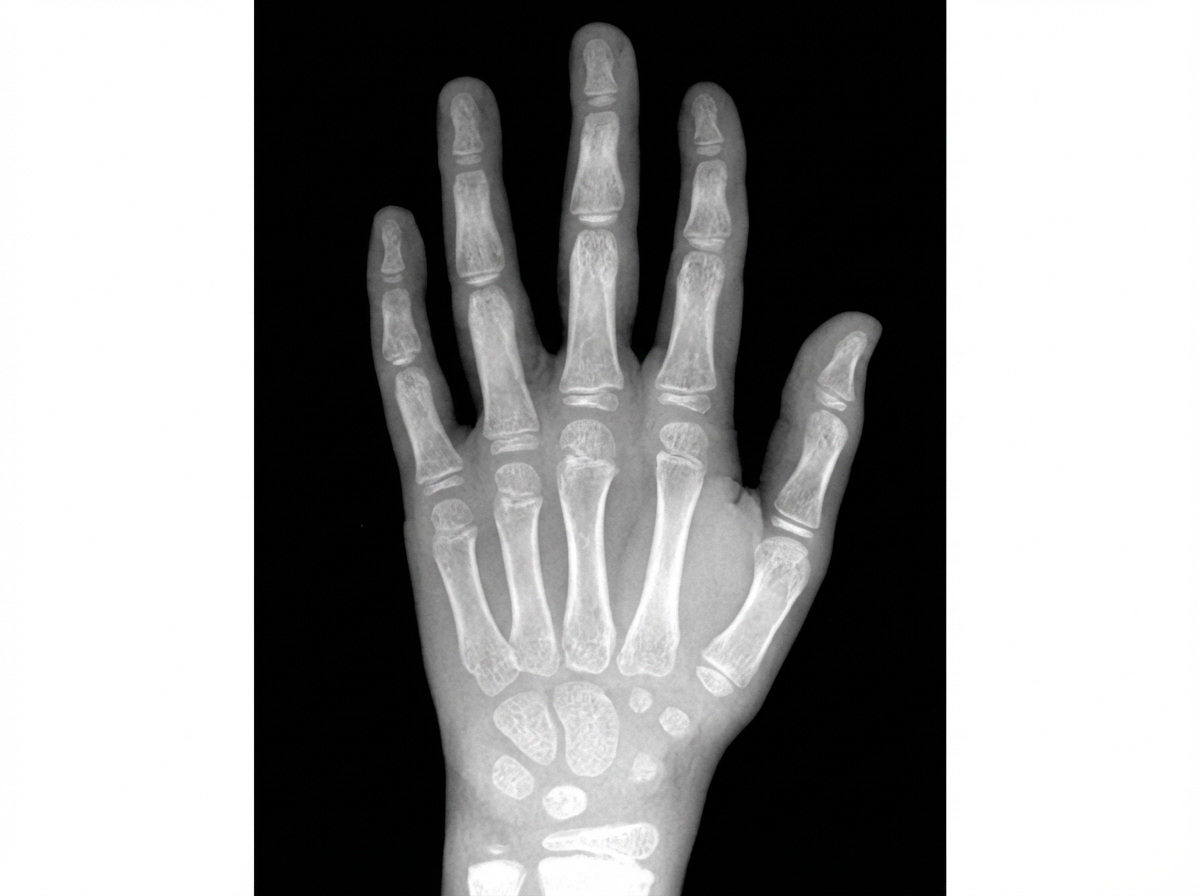

By examining the provided X-ray of a wrist, determine the age of the patient.

Explanation: ***7 years*** - At 7 years, the **capitate**, **hamate**, **triquetral**, and **lunate** ossification centers are typically visible on wrist X-ray according to the **Greulich and Pyle atlas**. - The **radial epiphysis** appears around this age, and **growth plates** remain wide open, consistent with normal 7-year developmental patterns. *6 years* - At 6 years, only the **capitate** and **hamate** are consistently ossified, with **triquetral** ossification just beginning or absent. - The **radial epiphysis** has not yet appeared, and fewer **carpal ossification centers** would be visible compared to the presented X-ray. *8 years* - At 8 years, additional ossification centers like the **scaphoid** and **trapezium** would typically be visible on X-ray. - The **ulnar epiphysis** begins to appear around this age, which would not match the developmental stage shown in this X-ray. *9 years* - At 9 years, most **carpal bones** including **scaphoid**, **trapezium**, and **trapezoid** would be clearly ossified and visible. - The **pisiform** ossification center may begin to appear, representing more advanced skeletal maturation than demonstrated in this X-ray.